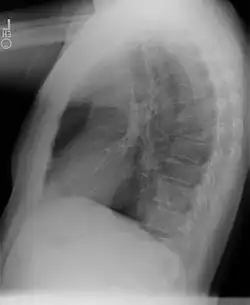

Chest radiograph

• Sequestrations typically appear as a uniformly dense mass within the thoracic cavity or pulmonary parenchyma.

• Recurrent infection can lead to the development of cystic areas within the mass.

• Air-fluid levels due to bronchial communication can be seen.